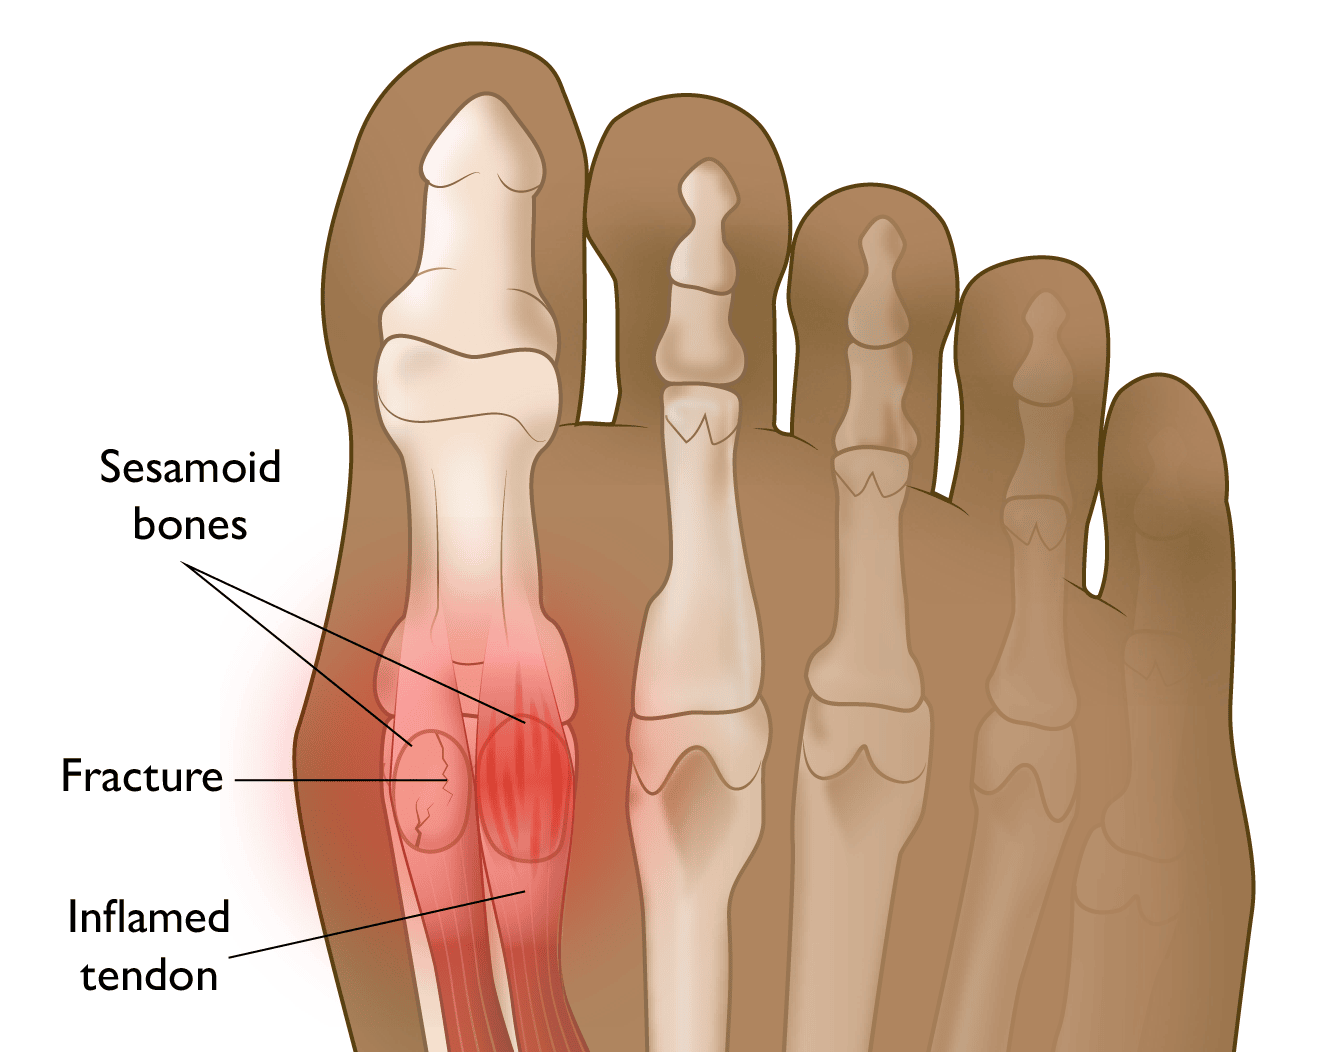

No pé, os sesamoides são dois ossinhos bem pequenos, do tamanho de um grão de feijão, localizados na parte de baixo da cabeça do primeiro metatarso – que é o osso longo que liga a parte do meio do pé ao seu dedão (hálux). Eles ficam mergulhados dentro dos tendões que passam por ali, e não se conectam diretamente a outros ossos através de articulações típicas, por isso são chamados de ossos "flutuantes".

Agora que sabemos a importância dos sesamoides, fica mais fácil entender o que acontece quando eles começam a doer. A sesamoidite nada mais é do que a inflamação desses ossos sesamoides e/ou dos tendões que os envolvem, gerando dor na parte de baixo do dedão do pé.

Existe fratura de sesamoide? Qual a diferença entre fratura e sesamoide bipartido?

Sim, os sesamoides são ossos e, como qualquer outro osso do corpo, podem fraturar. A fratura do sesamoide pode ocorrer de duas maneiras principais:

- Fratura aguda: Causada por um trauma direto e súbito, como um pisão, a queda de um objeto pesado sobre o pé, ou um movimento brusco e de alto impacto. A dor costuma ser forte e imediata.

- Fratura por estresse: Mais comum em atletas, acontece devido ao estresse repetitivo e contínuo sobre o osso, que vai gerando microlesões até que uma rachadura ou fratura completa ocorra. A dor, neste caso, desenvolve-se gradualmente.